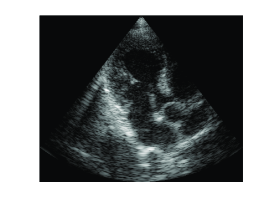

To demonstrate the equivalence of beamforming in time and frequency, we applied both methods on in vivo cardiac data yielding the images shown in Fig. 3. The imaging setup is that described in Section II-B with MHz. As can be readily seen, the images look identical.

(a)

(b)

A significant drawback of this method is its inability to restore weak reflectors. In the context of this approach they are treated as noise and are disregarded by the signal model. As a result, the speckle - granular pattern that can be seen in Fig. 3 - is lost. This severely degrades the value of the resulting images since information carried by speckle is of major importance in many medical imaging modalities. For example, in cardiac imaging, speckle tracking tools allow to analyze the motion of heart tissues and to track effectively myocardial deformations [21], [22].